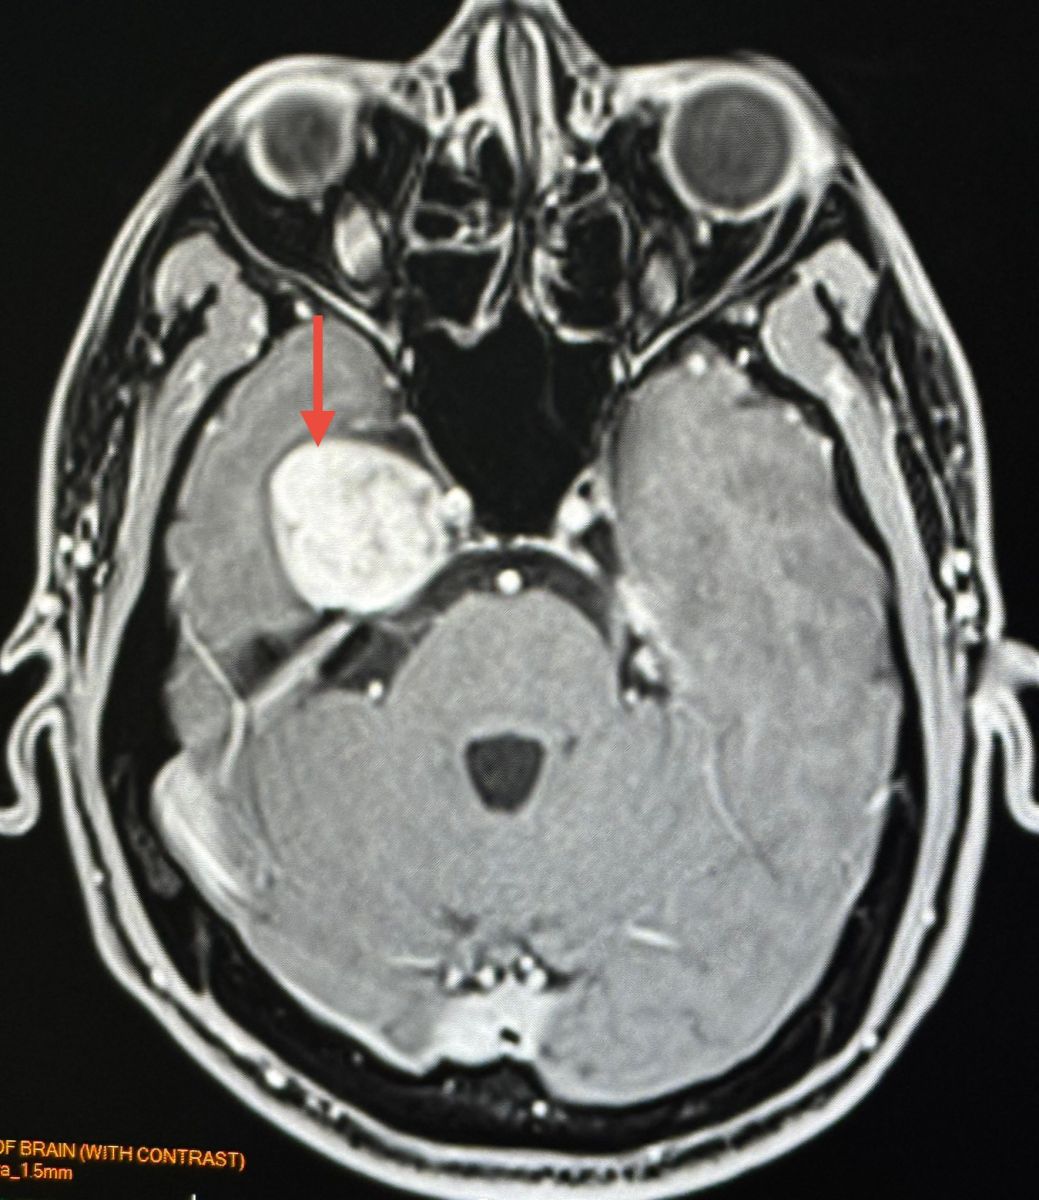

ทำคอมพิวเตอร์ CT สมองพบก้อนขนาด 2.7 × 3.0 × 2.9 เซนติเมตร ที่กลีบขมับของสมองด้านขวา right temporal lobe ทำ MRI (Magnetic Resonance Imaging) โดยใช้คลื่นแม่เหล็กไฟฟ้าและคลื่นวิทยุความถี่สูงและฉีดสี พบก้อนขนาด 3.1 × 2.9 × 2.9 เซนติเมตร สงสัย Trigeminal Schwannoma เนื้องอกของปลอกประสาทเส้นประสาทสมองเส้นที่ 5 ข้างขวา

อาการปวดศีรษะหายเอง ไม่ปวดอีกเลย ผู้ป่วยมีเนื้องอกในสมอง ตรวจเจอโดยบังเอิญจากการทำคอมพิวเตอร์สมอง